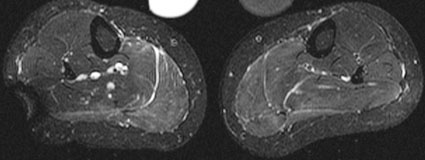

Abzugrenzen von dieser schwerwiegenden Muskelentzündung sind reaktive Veränderungen nach sportlicher Betätigung, die sich auch mit ödematösen muskulären Veränderungen manifestieren können. Dies wird im Fall einer 31-jährigen gesunden Frau in den STIR-MR-Bildern demonstriert (B). Auch diese leichtgradigen ödematösen Veränderungen in der Unterschenkelbeugemuskulatur beidseits kann die MRT sehr sensitiv erfassen (B), die krankheitsspezifische Einordnung ist anhand rein morphologischer Kriterien oft schwierig.